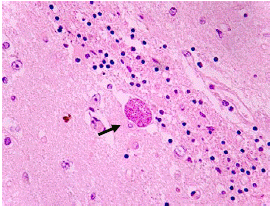

A pesar del tratamiento, la paciente evolucionó rápidamente a una falla orgánica múltiple y falleció a los diez días del ingreso. Se hizo la autopsia y en el estudio histopatológico de tejido miocárdico, cerebral y de músculo esquelético, se encontraron quistes tisulares con formas sugestivas de bradizoítos de Toxoplasma gondii (figura 3 4, 5 6, 7). Estos se sometieron al estudio de inmunohistoquímica utilizando el anticuerpo monoclonal específico para la proteína de membrana P30 de T. gondii (Novocastra™, clon TP3), purificado a partir de líquido ascítico de ratón y diluido en una solución tampón de fosfato salino (PBS), pH 7,6, con albúmina de suero bovino (BSA) al 1 % y 0,09 % de azida de sodio, cuyo resultado confirmó la presencia del parásito en los tejidos evaluados (figuras 8-9-10).

Figura 6 Tejido cerebral con necrosis focal y quiste con formas sugestivas de bradizoítos (flecha). Hematoxilina y eosina, 40X.